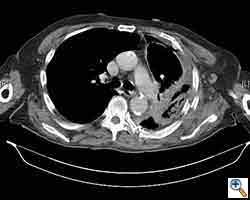

Here we present, as a paradigm of repair, the case of a 65 year old gentleman referred to our institution for an indolent mass in the left anterior chest wall. Repairs for other conditions follow the same rules. This mass had been stable in size for more than 12 months and the patient was prompted to seek medical attention as, after weight loss due to dieting, he felt the mass was uncomfortable while sleeping. Apart from coronary stenting for angina, the past medical history was unremarkable.

Computed tomography scan of the chest showed a mass protruding from the cortex of the third rib. A percutaneous core biopsy was non-diagnostic. We proceeded to an open incisional biopsy. This was reported as showing a spindle cell neoplasm. The patient was therefore scheduled, after multidisciplinary meeting discussion, for radical surgery.

At surgery, the mass was arising from the cortex of the third rib, and solid measuring 5x8 cm. There was no macroscopic involvement of the surrounding extra-thoracic musculature or of the underlying lung, the mass being confined to the rib and intercostal muscles. The patient underwent resection of the second to fourth ribs and the rhomboid muscle as well, in the attempt to get clear margin. The large antero-lateral defect was eventually reconstructed using 2 mouldable titanium bars. To prevent lung herniation through the defect, we reconstructed the layers anatomically using a biological patch (Veritas®). The final histopathology was a low grade sarcoma of the chest wall with clear resection margins.

He made an excellent recovery with daily physiotherapy to encourage shoulder movements. He was discharged with oral analgesia on postoperative day 4. At 1-month follow-up the patient had no pain at all, discontinued analgesia on postoperative day 17 and demonstrated a full range of shoulder movement. His chest x-ray was unremarkable and the wound healed without complication.